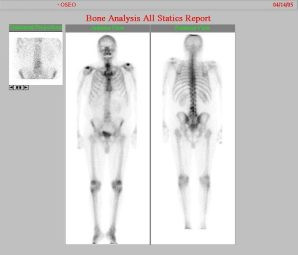

Metástasis óseas por cáncer de prostata

Envíado por Instituto Nacional de Cardiología y Cirugía Cardiovascular